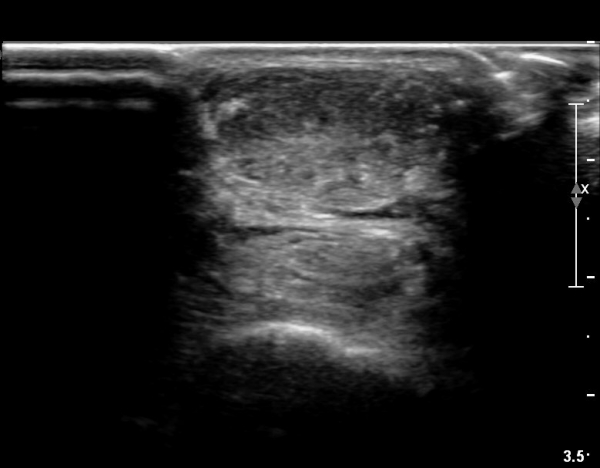

³»Ãø ºñº¹±Ù Á¾´Ü¸é°Ë»ç¿¡¼­ ³»Ãø ¹èº¹±Ù ¸»´ÜºÎ ÆÄ¿­°ú °¡Àڹ̱٠½ÉºÎ¿¡ ¼ö¾×Àú·ù°¡ °üÂûµÊ(»çÁø 1, 2).

¾ÆÅ³·¹½º°Ç Á¾´Ü¸é°Ë»ç¿¡¼­ ¾ÆÅ³·¹½º°Ç ¸»´ÜºÎ¿¡ ¾ÆÅ³·¹½º°ÇÀÇ Àú¿¡ÄÚºÎÁ¾, ±¹¼ÒÀû ¿¬°á¼º ¼Ò½Ç,

¹ß¸ñ°üÀý ÈĹæºÎ¿¡ ¼ö¾×Àú·ù°¡ °üÂûµÊ(»çÁø 3, 4, 5).